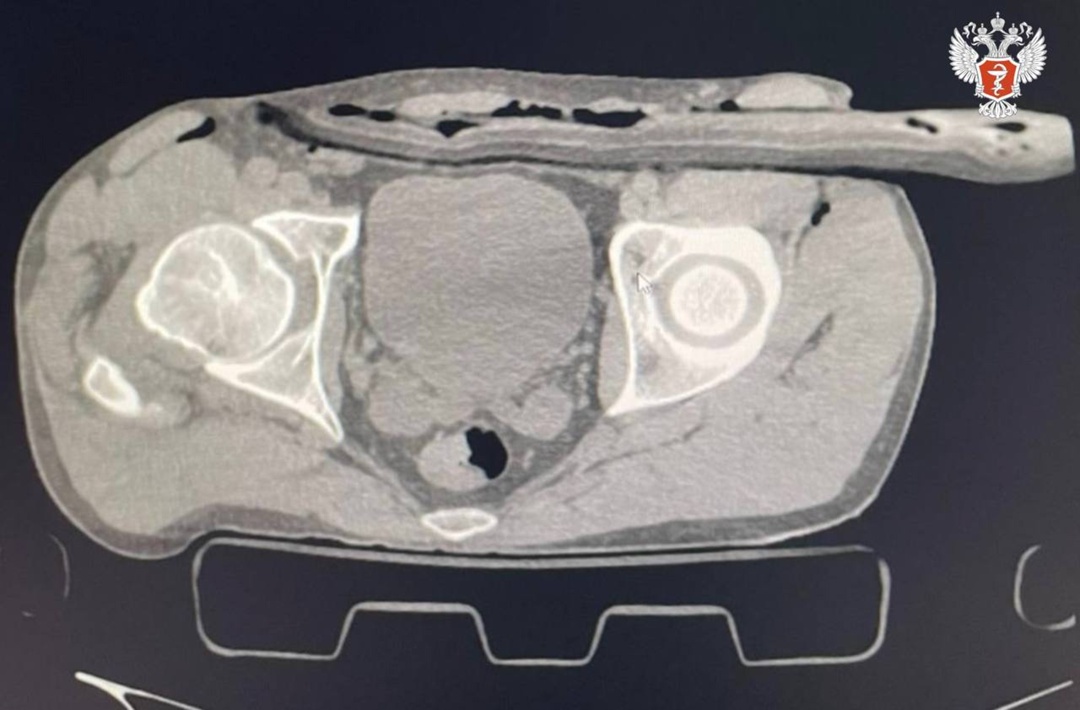

42-летний пациент был доставлен в Солнечногорскую больницу после того,как в результате ремонтирования крыши загородного дома упал на дерево, напоровшись на сук. Ветка прошла через бедро в толщу брюшной стенки.

➡️ Врачи провели компьютерную томографию и УЗИ, которые показали наличие свободной жидкости в животе.